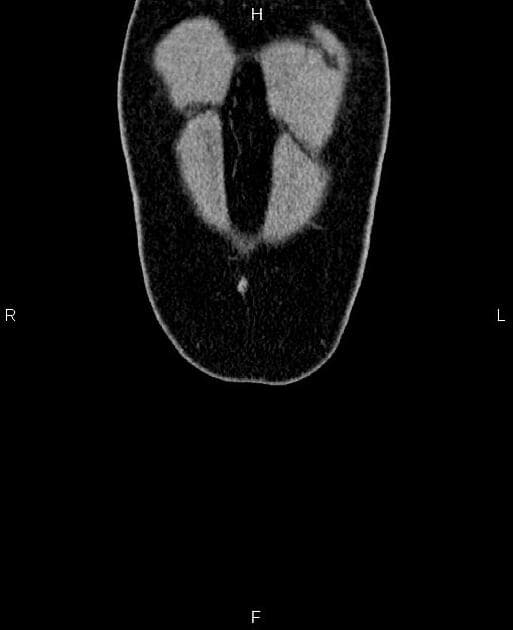

Coronal T2

- Một khối nang khu trú một phần lồi ra ngoài (exophytic) kích thước 48 mm, thành dày ngấm thuốc (enhancement) và có các vách ngăn cùng các nốt ngấm thuốc lệch tâm (eccentric enhancing nodules) được ghi nhận ở phần giữa của thận phải.

Khối nang thận - phân loại Bosniak IV (Renal cystic mass - Bosniak class IV)

- "Các đặc điểm hình ảnh chính bao gồm thành dày ngấm thuốc, vách ngăn ngấm thuốc và các nốt ngấm thuốc lệch tâm."